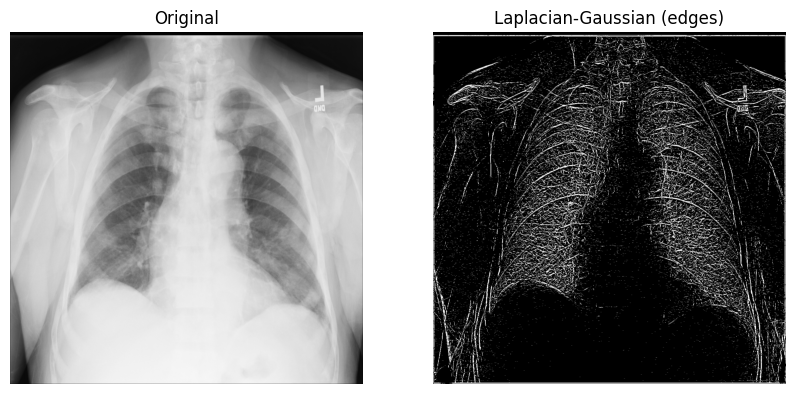

The Laplace filter with Gaussian second derivatives¶

Let’s start with an n-dimensional Laplace filter (“Laplacian-Gaussian”) that uses Gaussian second derivatives. This Laplacian method focuses on pixels with rapid intensity change in values and is combined with Gaussian smoothing to remove noise. Let’s examine how it can be useful in analyzing 2D X-ray images.

The implementation of the Laplacian-Gaussian filter is relatively straightforward: 1) import the

ndimagemodule from SciPy; and 2) callscipy.ndimage.gaussian_laplace()with a sigma (scalar) parameter, which affects the standard deviations of the Gaussian filter (you’ll use1in the example below):

from scipy import ndimage

xray_image_laplace_gaussian = ndimage.gaussian_laplace(xray_image, sigma=1)Display the original X-ray and the one with the Laplacian-Gaussian filter:

fig, axes = plt.subplots(nrows=1, ncols=2, figsize=(10, 10))

axes[0].set_title("Original")

axes[0].imshow(xray_image, cmap="gray")

axes[1].set_title("Laplacian-Gaussian (edges)")

axes[1].imshow(xray_image_laplace_gaussian, cmap="gray")

for i in axes:

i.axis("off")

plt.show()